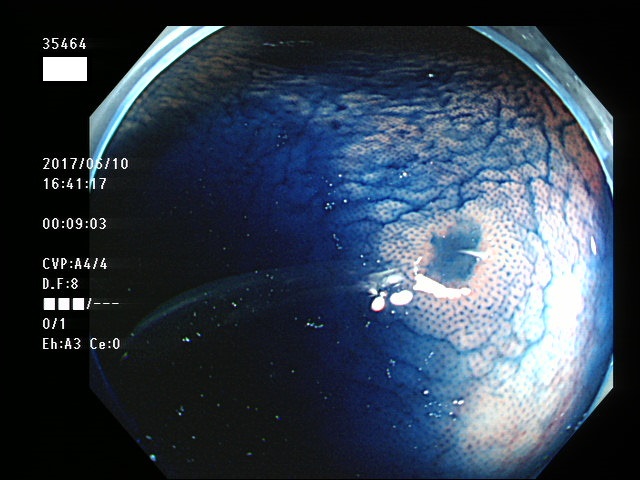

上記100名より抽出した平坦・陥凹型腺腫・SSAP(=癌化の危険が高いが見落としやすい病変)の内視鏡写真

35403 35404 35405 35409 35410 35412 35413 35414 35416 35417 35418 35419 35420 35421 35426 35429 35430 35433 35434 35435 35438 35439 35440 35444 35445 35447 35449 35450 35451 35452 35453 35454 35458 35460 35463 35464 35466 35468 35469 35470 35472 35473 35478 35479 35481 35483 35485 35489 35490 35491 35492 35493 35498 ・・・・・の54名